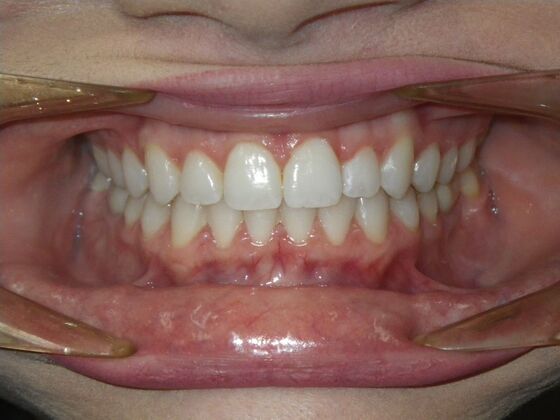

Invisalign: Case 17

This patient was an awesome dental assistant for our practice and we were all very sad when she had to move closer to her home. She was very interested in correcting some minor spacing and rotations in her upper and lower anterior teeth and to decrease her overbite as well.Treatment took about 12 months, but we were pleased with the results and fabricated clear invisalign vivera retainers. We are still hoping one day she will return to be with us again.